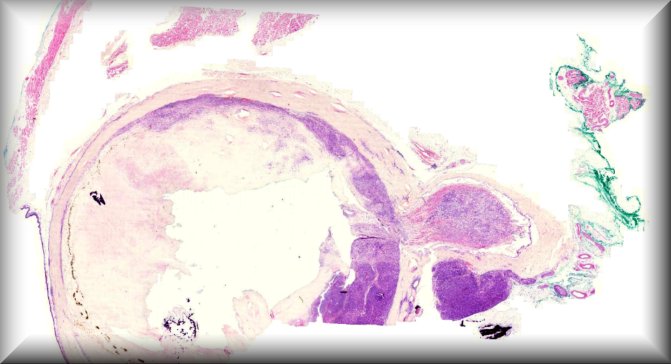

Hind M. Alkatan (Guest): A 10-month-old boy presented with a painless scrotal mass.External examination demonstrated left scrotal non-tender hard mass measuring 4x3 cm in size, with negative transillumination test. Ultrasonography of left scrotum showed a well-circumscribed, oval shaped mass with mixed echogenicity, The mass contained both cystic and solid component, with no clear visualization of the left testicle.The patient underwent left scrotal exploration with high inguinal orchidectomy |